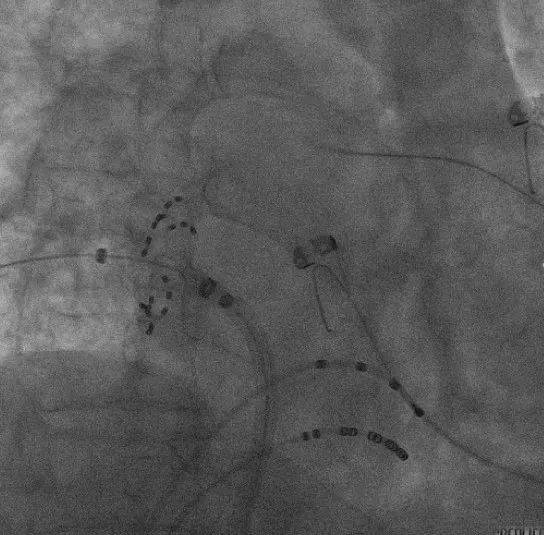

ICE引导消融导管位置:

血流模式确认左上肺静脉

血流模式确认左下肺静脉

LSPV消融:

LSPV口内消融_ICE直视下脉冲导管以网篮形态与肺静脉贴靠

LSPV前庭消融_ICE直视下,显示脉冲导管以花瓣形态与肺静脉贴靠

LIPV消融:

ICE直视下,PFA导管进行左下肺静脉贴靠消融